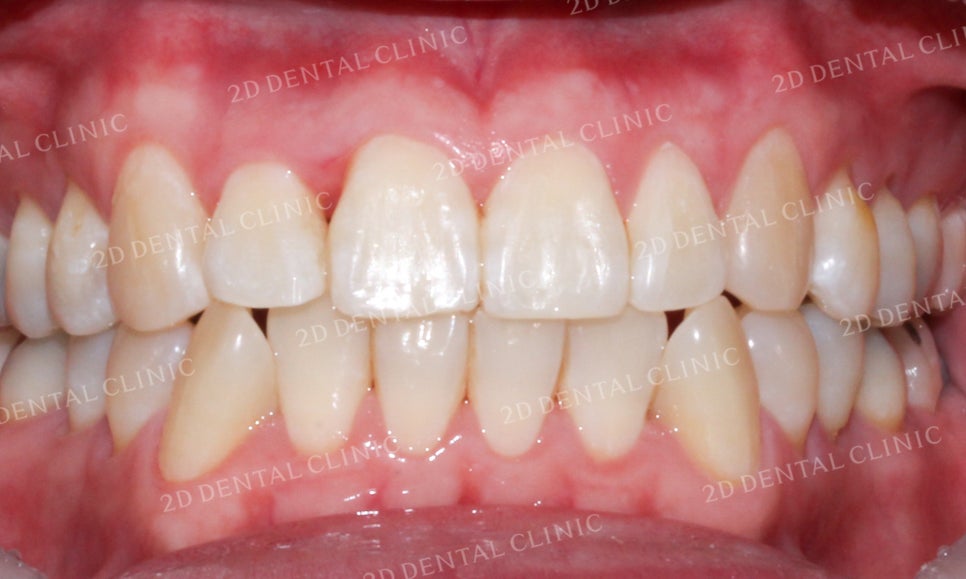

<Before> <After>

![[앞니교정]부정교합교정, 부분교정으로 완성하기! by.투디치과(2D치과) 관련 이미지 13](https://pub-9f2bb3498faf4d1d8714b41df24753e3.r2.dev/content/clinics/archive/grb36g4zmx/naver_blog/dental2d/assets/by_hash/a3c176ae2209043d1f663cff16e15d6c785914465eaedef70c0e4b85fa91096c.jpg)

![[앞니교정]부정교합교정, 부분교정으로 완성하기! by.투디치과(2D치과) 관련 이미지 14](https://pub-9f2bb3498faf4d1d8714b41df24753e3.r2.dev/content/clinics/archive/grb36g4zmx/naver_blog/dental2d/assets/by_hash/9bfea7a81831b1eaf5cf8a7838de5e741a174299c3ffaba925cee4c34742296d.jpg)

[앞니교정]부정교합교정, 부분교정으로 완성하기! by.투디치과(2D치과)

전체적으로 치열이 고르지 않고

삐뚤거리던 전치부 또한

부분교정 후 비교적 고르게 바뀐 모습이네요!